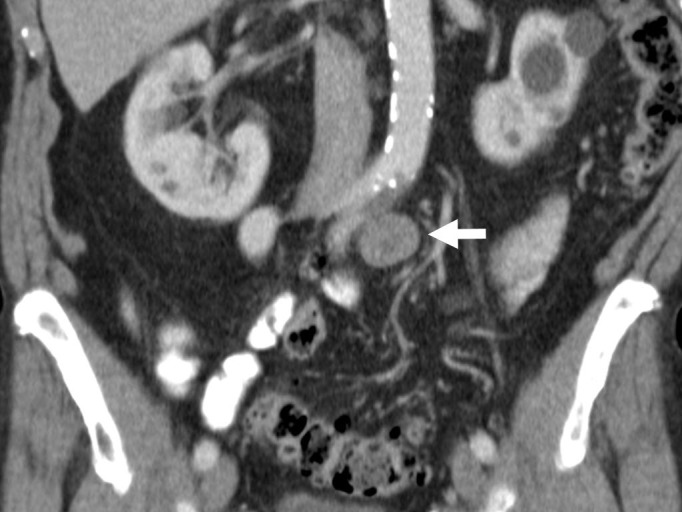

Materials: we present the case of an 82-year-old male patient with a recent diagnosis of moderately differentiated adenocarcinoma of the colon and a hypermetabolic periaortic nodule as an incidental finding.

Results: percutaneous biopsy of the periaortic nodule confirmed the diagnosis of schwannoma. At one year of follow-up, growth of the schwannoma has been demonstrated. There are no signs of progression of his oncological disease.

Conclusions: schwannomas are benign tumors, rarely found in the retroperitoneum and can be sources of false-positive positron emission tomography results.